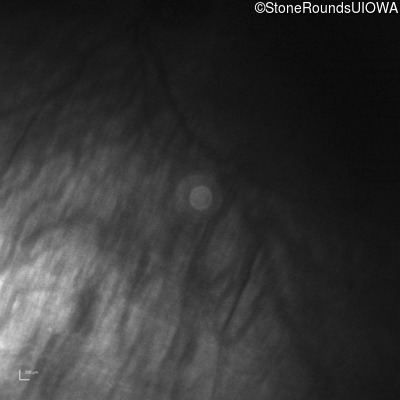

Infrared Fundus Photograph - Right -

No Light Perception

Exemplar

Infrared Fundus Photograph - Left -